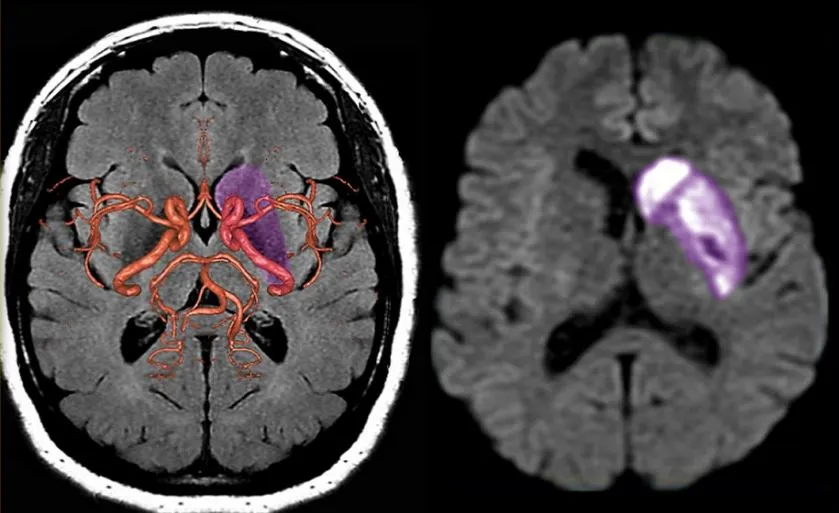

서양 의학에서는 이 중풍을 동맥경화로 인한 뇌출혈 또는 막힌 것이라고 하는데 이 두 가지 다 겉에서는 반신(半身)을 못쓰게 되는 것이다.

현대의학에서는 뇌졸중 또는 중풍의 기초적 질환을 고혈압증이나 동맥경화증으로 본다. 동맥경화라고 하는 것은 동맥의 벽이 굳어지는 상태. 즉, 동맥의 노화 현상이다. 우리의 일생 중에 받은 다수의 화학적, 기계적 자극 또는 장애가 축적된 결과인 것이다.

동맥경화는 지금 말한 바와 같이 동맥의 아무 곳에나 생기지만 뇌동맥에 생기면 뇌졸중의 원인이 되고, 관상동맥에 생기면 심근경색이나 협심증이 된다. 또 신장에서 심하게 생기면 신경화증을 나타내고, 하지동맥에 생겨서 혈행(血行)이 저해되면 걸어갈 때 하지가 아픈 병이 된다. 세동맥이라는 모세관 앞의 가는 동맥에 널리 경화가 생기면 고혈압의 원인이 되고, 그것이 또 기타의 동맥경화를 가져오는 악순환을 만들게 된다.